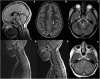

Relapsing demyelinating syndromes (RDS) in children encompass a diverse spectrum of entities including multiple sclerosis (MS) acute disseminated encephalomyelitis (ADEM), aquaporin-4 antibody associated neuromyelitis optica spectrum disorder (AQP4-NMOSD) and myelin oligodendrocyte glycoprotein antibody disease (MOG-AD). In addition to these, there are "antibody-negative" demyelinating syndromes which are yet to be fully characterized and defined. The paucity of specific biomarkers and overlap in clinical presentations makes the distinction between these disease entities difficult at initial presentation and, as such, there is a heavy reliance on magnetic resonance imaging (MRI) findings to satisfy the criteria for treatment initiation and optimization. Misdiagnosis is not uncommon and is usually related to the inaccurate application of criteria or failure to identify potential clinical and radiological mimics. It is also notable that there are instances where AQP4 and MOG antibody testing may be falsely negative during initial clinical episodes, further complicating the issue. This article illustrates the typical clinico-radiological phenotypes associated with the known pediatric RDS at presentation and describes the neuroimaging mimics of these using a pattern-based approach in the brain, optic nerves, and spinal cord. Practical guidance on key distinguishing features in the form of clinical and radiological red flags are incorporated. A subsection on clinical mimics with characteristic imaging patterns that assist in establishing alternative diagnoses is also included.